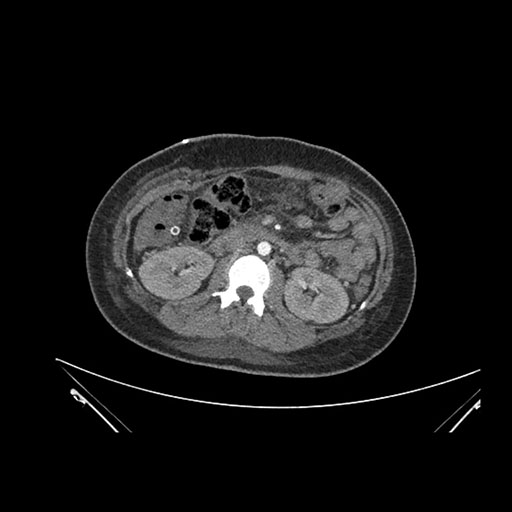

Axial Venous

Imaging analysis

Based on initial findings, which issue(s) would you be most concerned about?